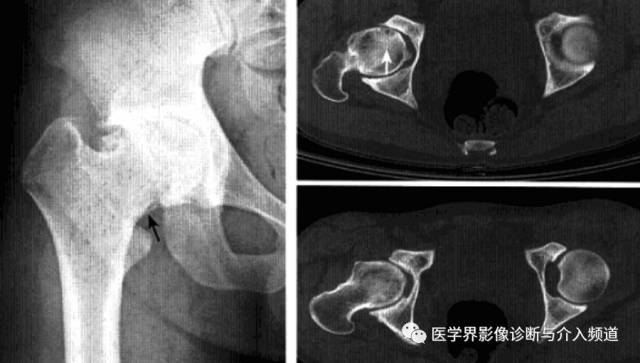

平片:①凸轮撞击型,正位片示头颈连接处扁平,呈“左轮枪柄”样畸形,侧位片示股骨头颈凹陷减少,中心边缘角变小<16度,②钳夹撞击型,髋臼窝过深,髋臼后倾,呈相交8字征,偏心距缩短<9mm。

CT:三维CT可测量股骨头颈连接处前外侧偏移量减低,股骨头颈联合处前上缘可见骨性突起。